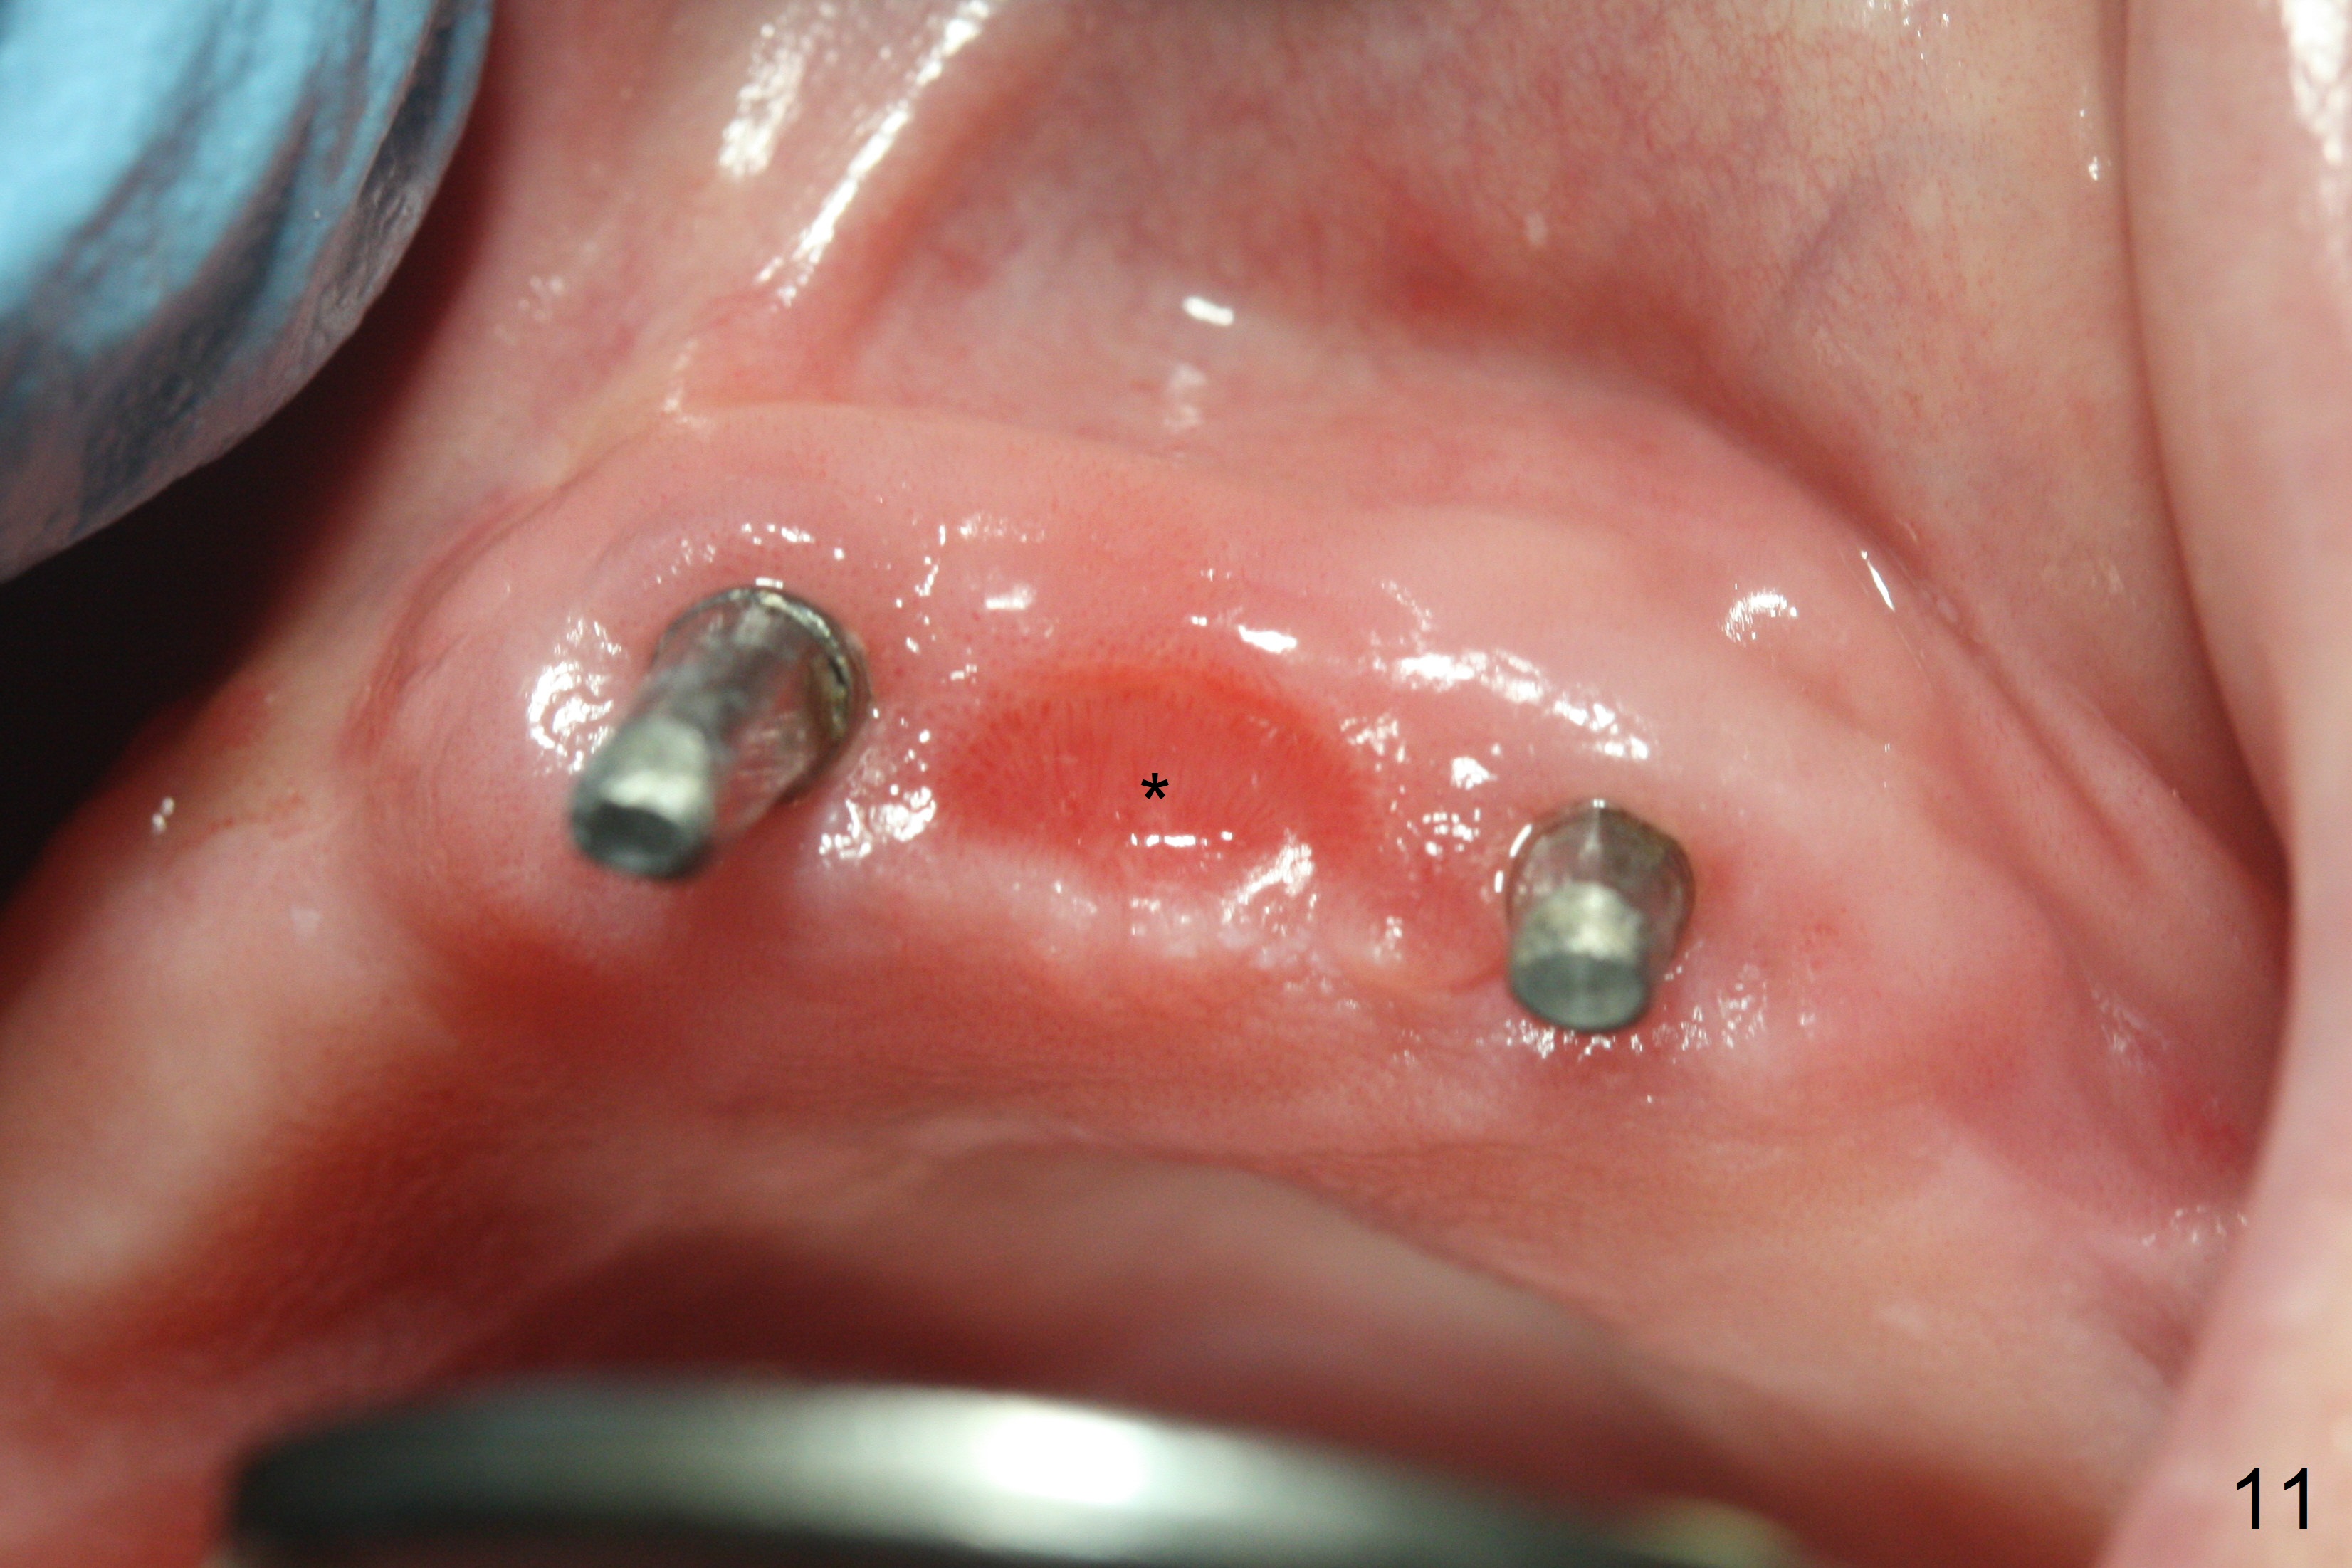

Incision reveals that the ridge at #9 and 11 is narrower than expected. A 3x14 mm 15º 1 piece implant is placed at the site of #9, while a 3x17 mm straight 1-piece one is placed at #11 (Fig.1,4). Insertion torques at #9 and 11 are 20 and 30 Ncm, respectively. The relatively low insertion torque is partially due to osteoporosis. The 65-year-old lady also has dry mouth. Osteotomy should be underprep. The position and trajectory of the implants are dictated by the partial denture (Fig.2). After minor abutment adjustment (Fig.3), an immediate provisional bridge is fabricated. There is no interference when the partial is removed and inserted. After bone graft (Fig.4 ^) and Osteogen Membrane, the ridge (Fig.3) is wider than before. The patient returns for reline 2 months postop (Fig.5-7). In spite of insufficient oral hygiene, the gingiva remains healthy around the implants. To form distinct papillae, acrylic should be added to (Fig.8 yellow line) and removed from (hushed area) the individual provisional crowns. One month after provisional modification (Fig.10, as compared to Fig.5), the pontic recipient site is concave (Fig.11) and becomes less concave after cord packing and abutment trimming. When the provisional bridge is reseated after impression (Fig.12), the pontic recipient site must be blanched again. Please trim the pontic recipient site of the model ~ .5 mm to enhance cosmetics. Water Pik has been used since surgery, but it may be related to loss of bone graft 3.5 months postop (Fig.9 *). One month post cementation, the patient has complained of pain when water pik is irrigating the gingiva palatal to the FPD, apparently in association with denture-related Candidiasis. Two weeks of use of Mycostatin Oral Suspension, peri-implantitis or peri-implant mucositis-like signs and symptoms disappear (Fig.13). CBCT taken 6 months postop confirms that the implants appear to be have been placed in the bone (14,15). The FPD appears to be loose 2.5 years post cementation.